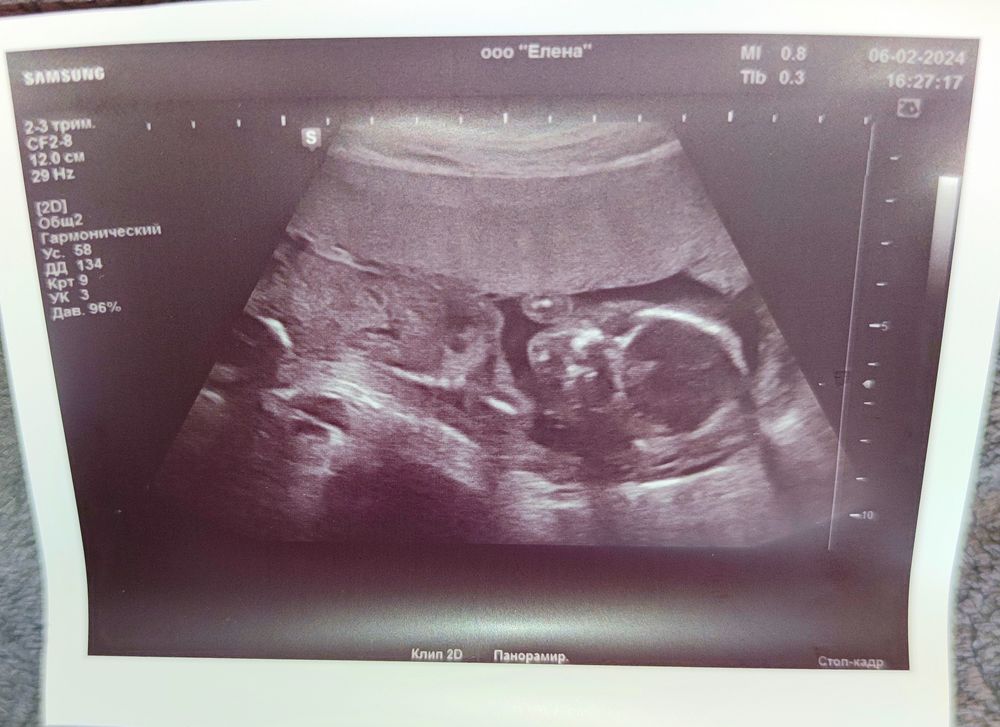

Кто будет мальчик или девочка?

Сложно, конечно, по такой фотографии определить, но срок позволяет, по тому, что я "вроде" вижу, предположу, что мальчик))

Не видно кто, но позирует замечательно😄🥰

Вроде как мальчик😁

Тут только личико видно)

Я думаю- мальчик 👦